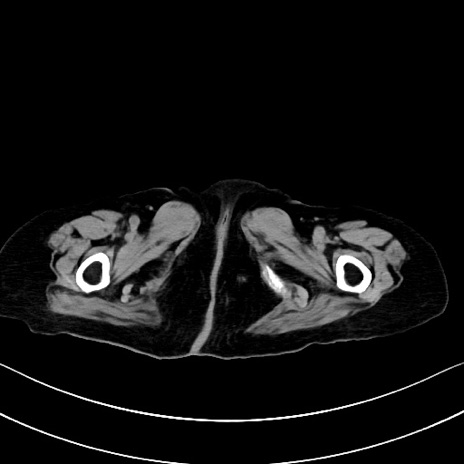

他院CT

冠状断像